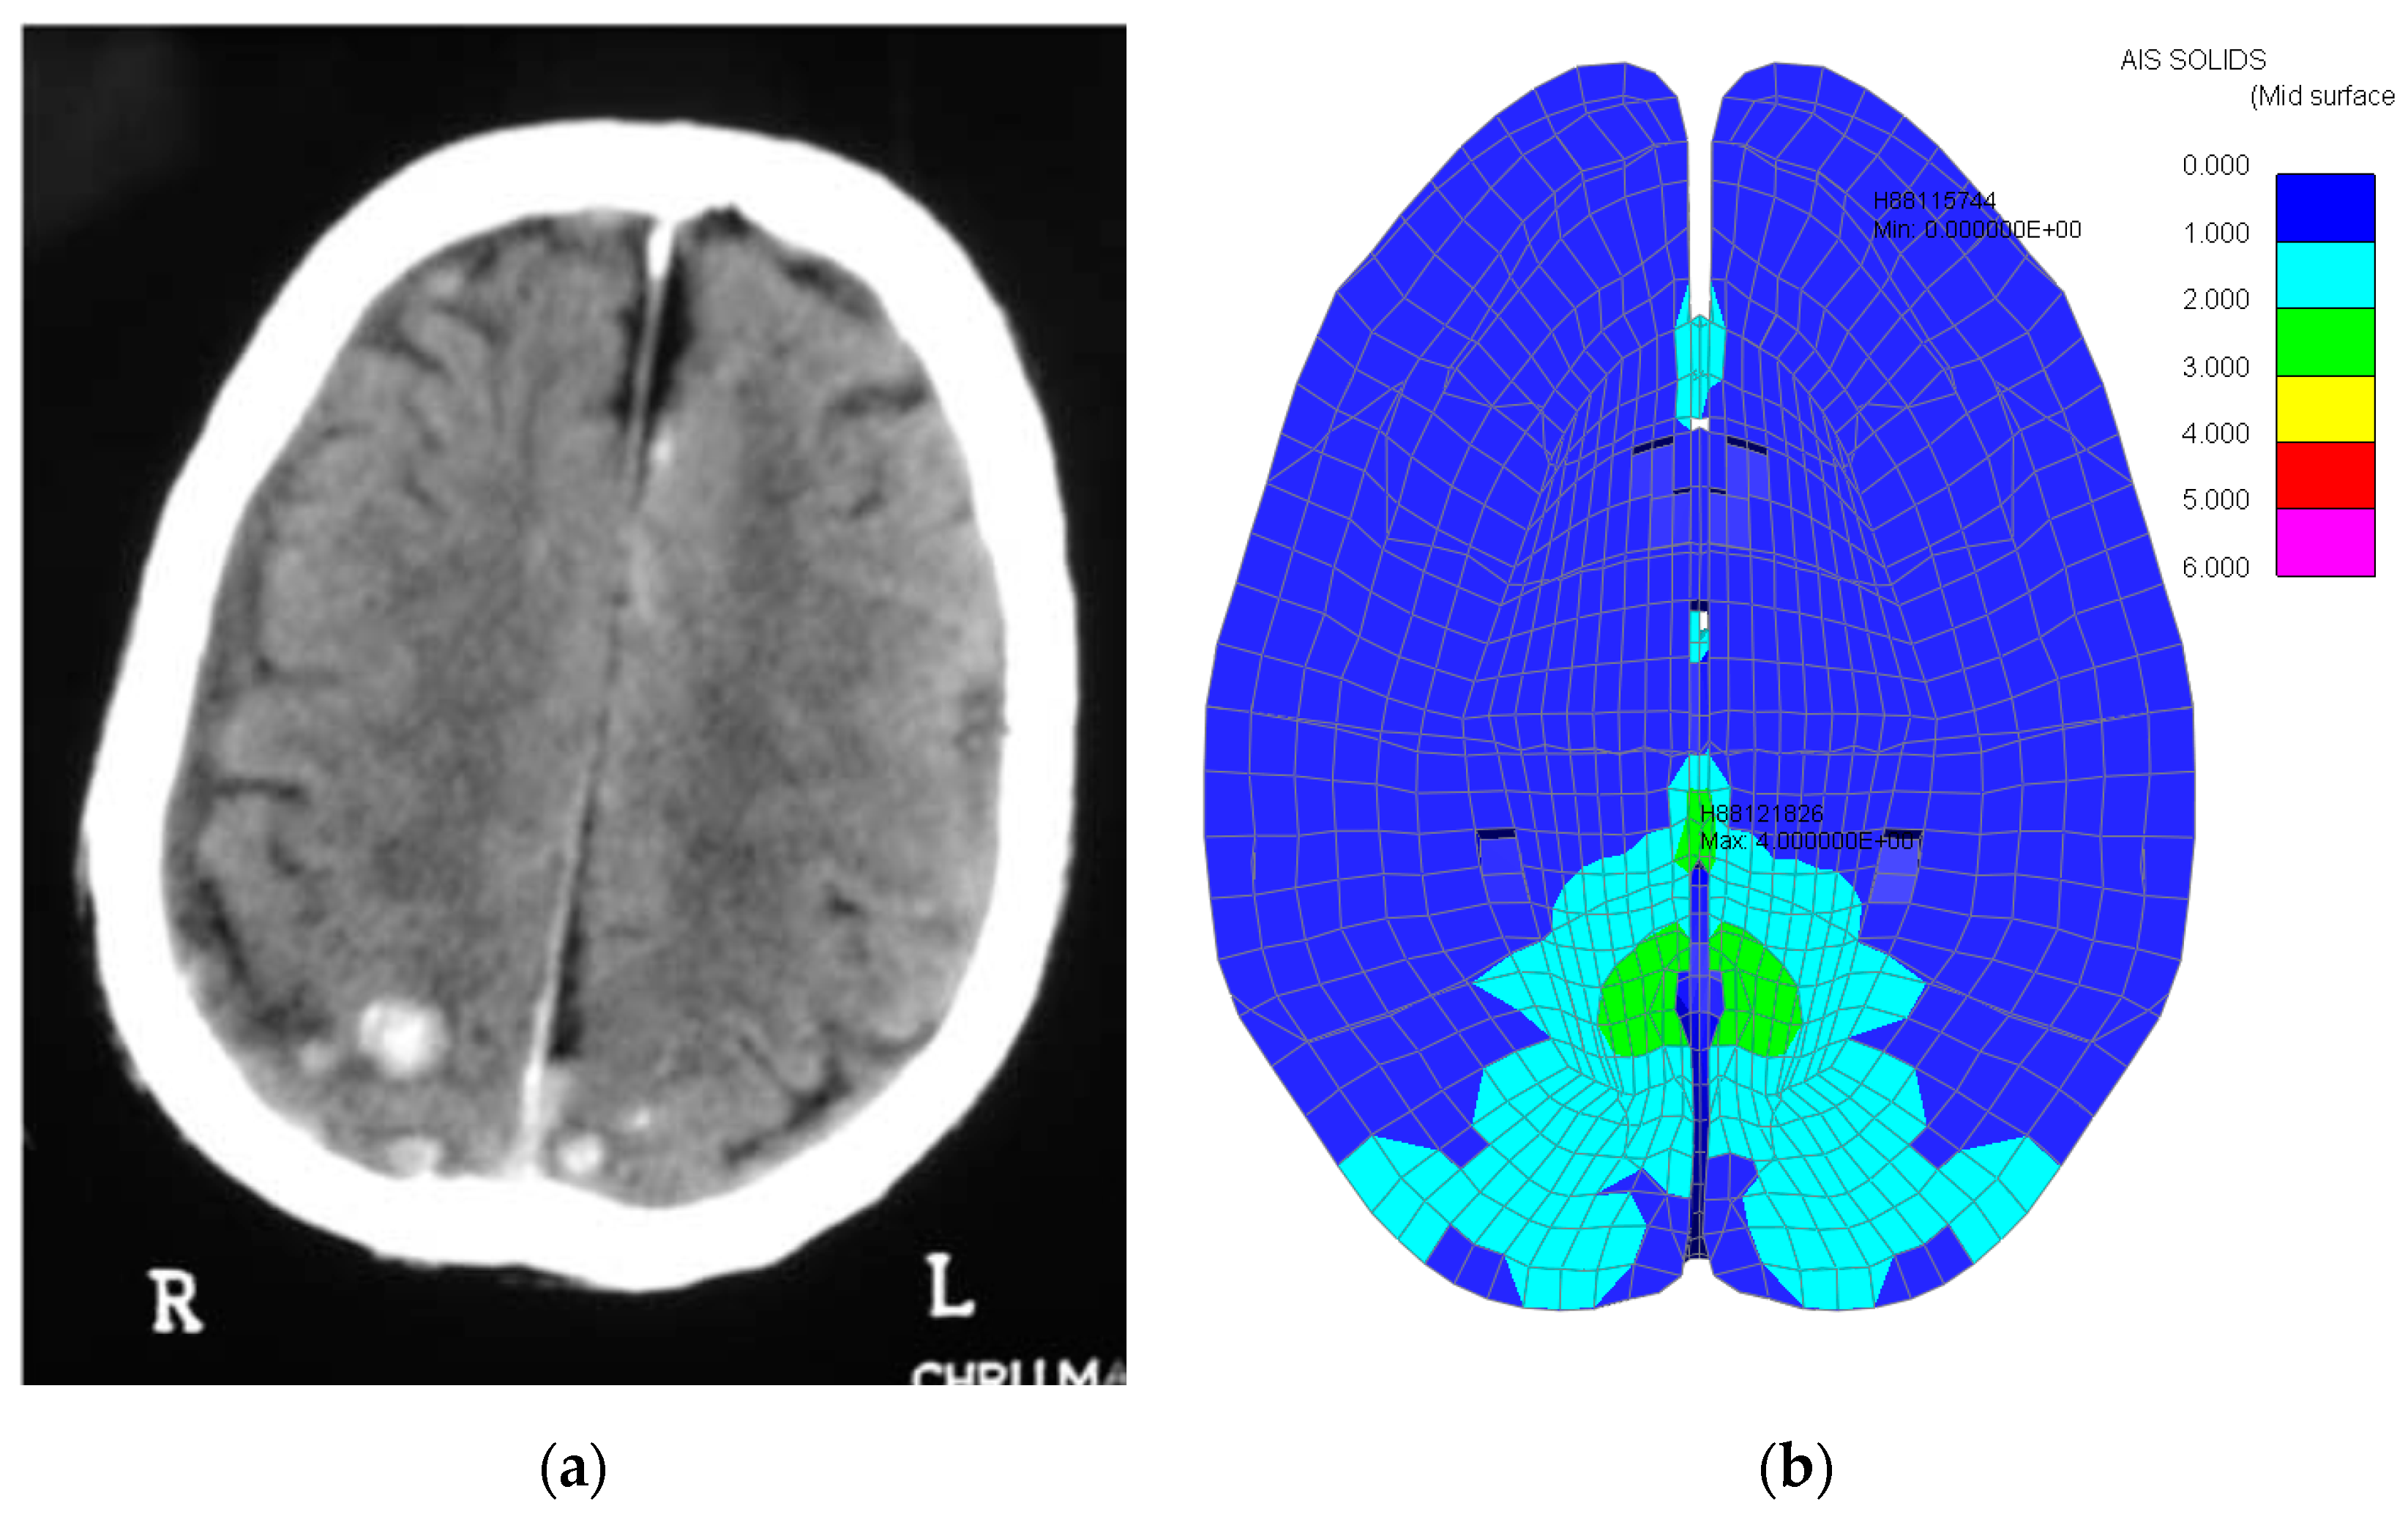

Figure 10.

Occipital Grey Matter OTM Model. (a) Occipital grey matter trauma prediction, (b) Maximum Principal strain (grey matter).

However, looking at the MPS values in the grey matter, its value exceeded 25.5% (Figure 10b); hence, a hemorrhage is present. Consequently, the AIS level is increased by +1, meaning that the final trauma severity computed in the grey matter is AIS 4.

3.1.2. White Matter

The PVP value computed was 5.03 mW, which is overlaid over the OTM model for an impact speed of 6.0 m/s. The trauma severity is, therefore AIS 4, as illustrated in Figure 11a.

Figure 11.

Occipital White Matter OTM Model. (a) Occipital white matter trauma prediction, (b) Maximum Principal strain (white matter).

However, looking at the MPS values in the grey matter, its value exceeded 25.5% (76.9%) (Figure 11b); hence, a hemorrhage is present. Consequently, the AIS level is increased by +1, meaning that the final trauma severity computed in the grey matter is AIS 5.